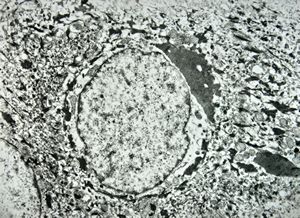

M, 11y. | mycosis fungoides v.s. - cerebriform nucleus of Sézary cell

F, 57y. | mycosis fungoides … cerebriform nucleus of Sézary cell

F, 37y. | mycosis fungoides … cerebriform nucleus of Sézary cell